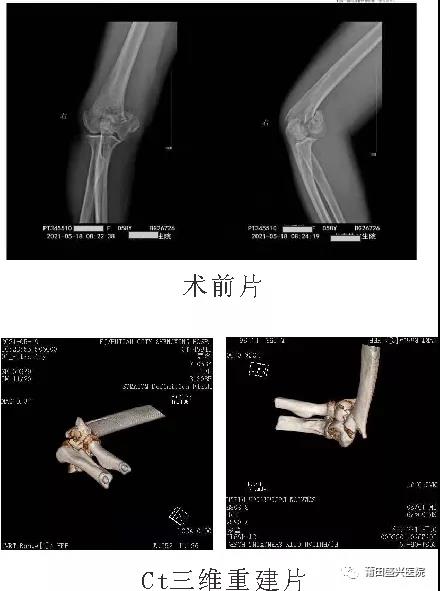

日前,有一女性患者王xx,右肱骨髁間粉碎性骨折,經(jīng)過與家屬及本人溝通后,我院業(yè)務(wù)副院長(zhǎng)林國(guó)兵為其采用在3D打印模型導(dǎo)引下,進(jìn)行切開復(fù)位接骨板螺釘內(nèi)固定手術(shù),取得成功,恢復(fù)肘關(guān)節(jié)滑車及髁關(guān)節(jié)面的平整,內(nèi)固定牢靠。近期已開始指導(dǎo)患者進(jìn)行功能鍛練。   林國(guó)兵,盛興醫(yī)院業(yè)務(wù)副院長(zhǎng),骨科副主任醫(yī)師、 副教授……